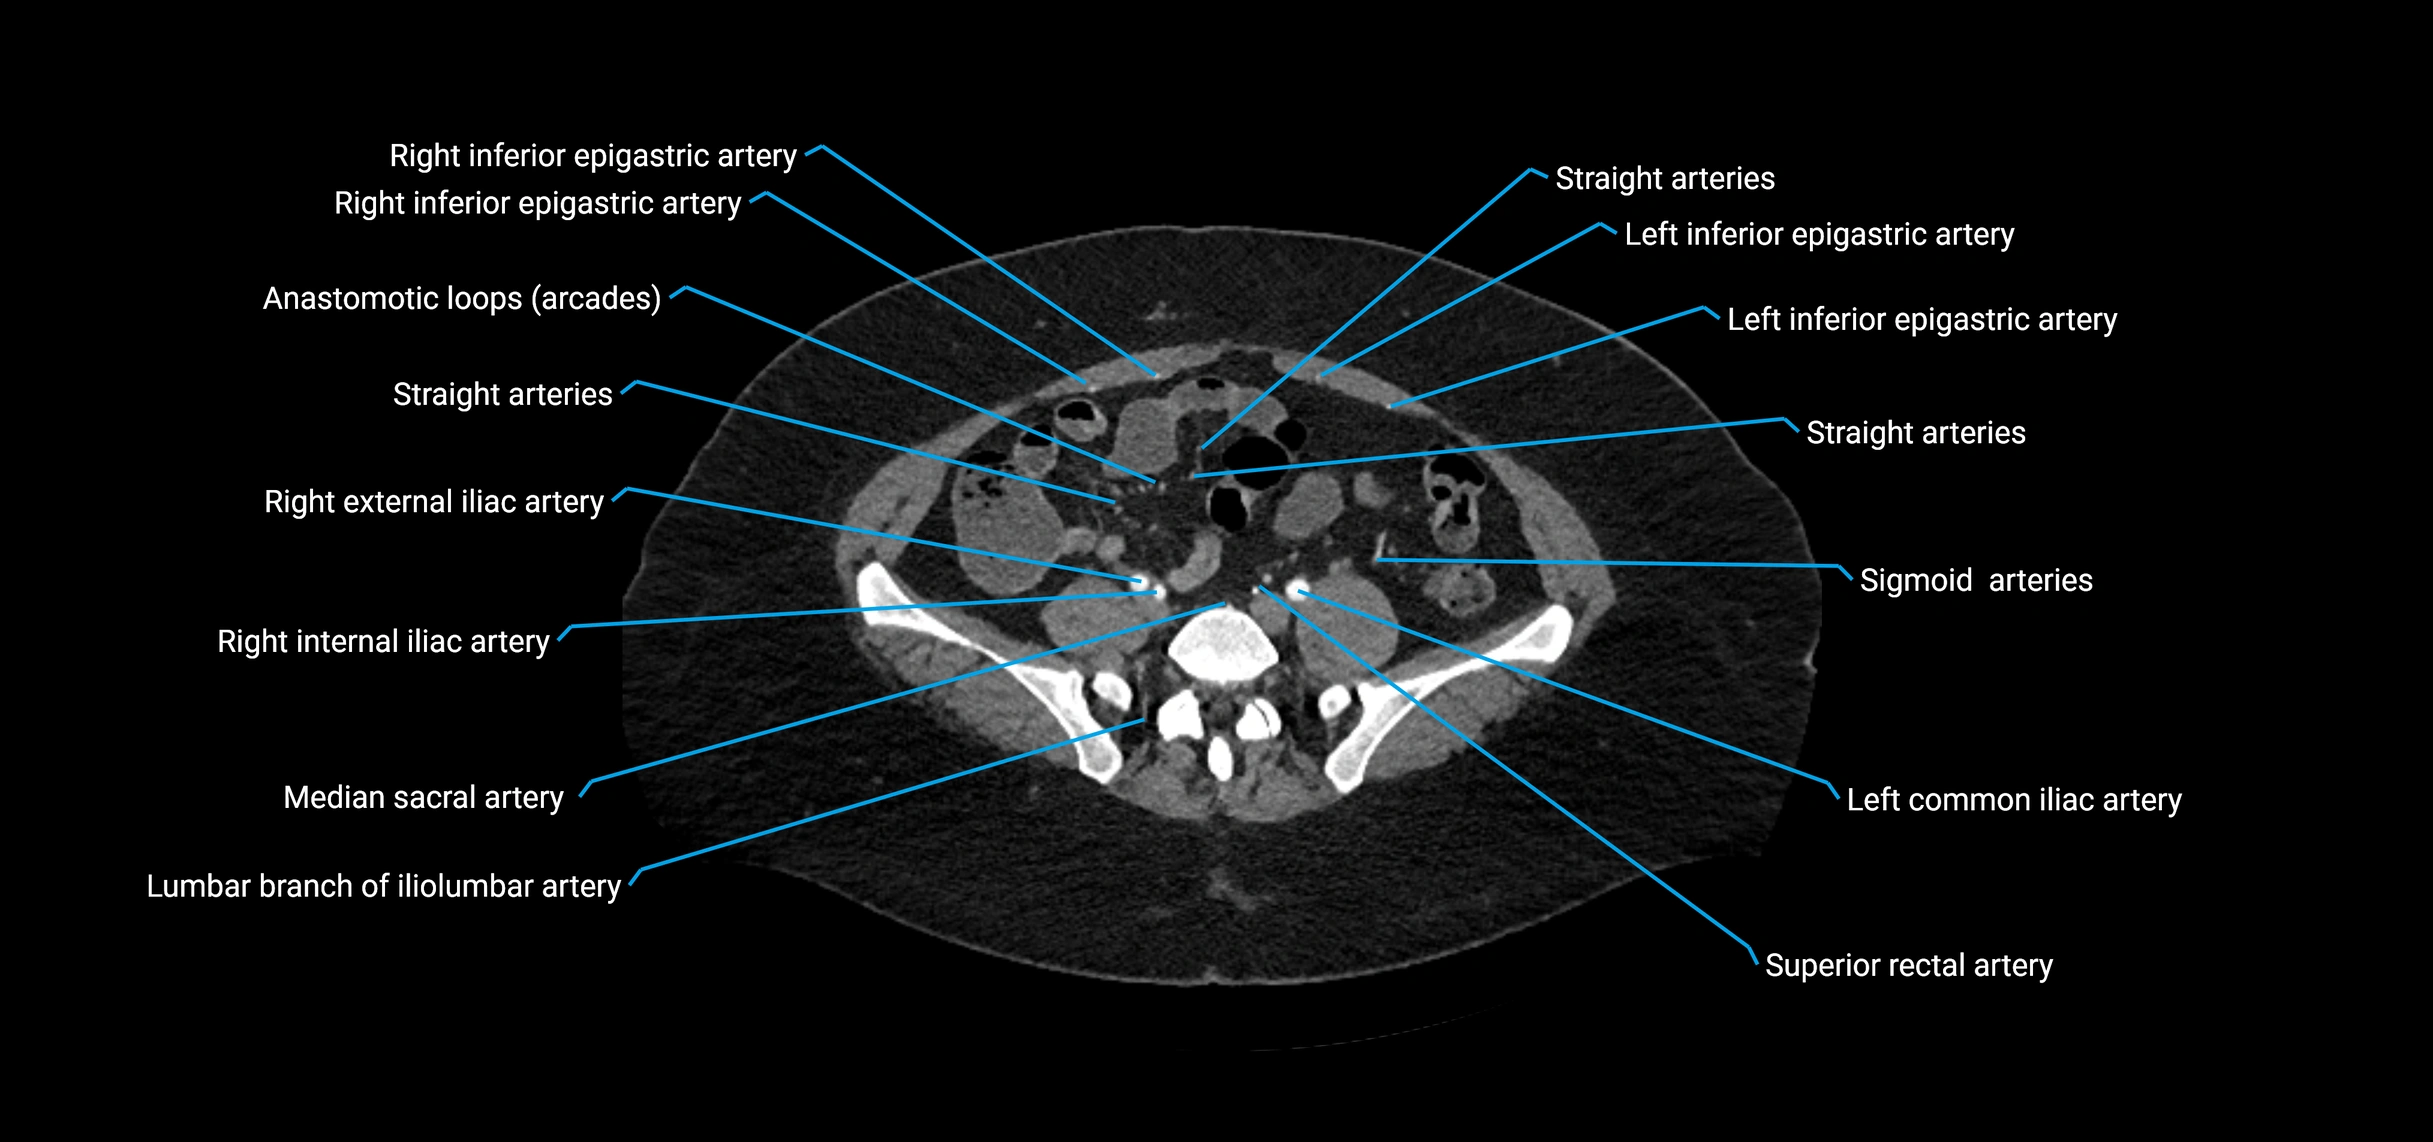

Contrast-enhanced CT (CTA):

• Gold standard for abdominal aortic imaging

• Provides excellent detail of lumen, wall, aneurysm, thrombus, and branch vessels

• Multiplanar and 3D reconstructions help in aneurysm measurement, stent graft planning, and dissection evaluation